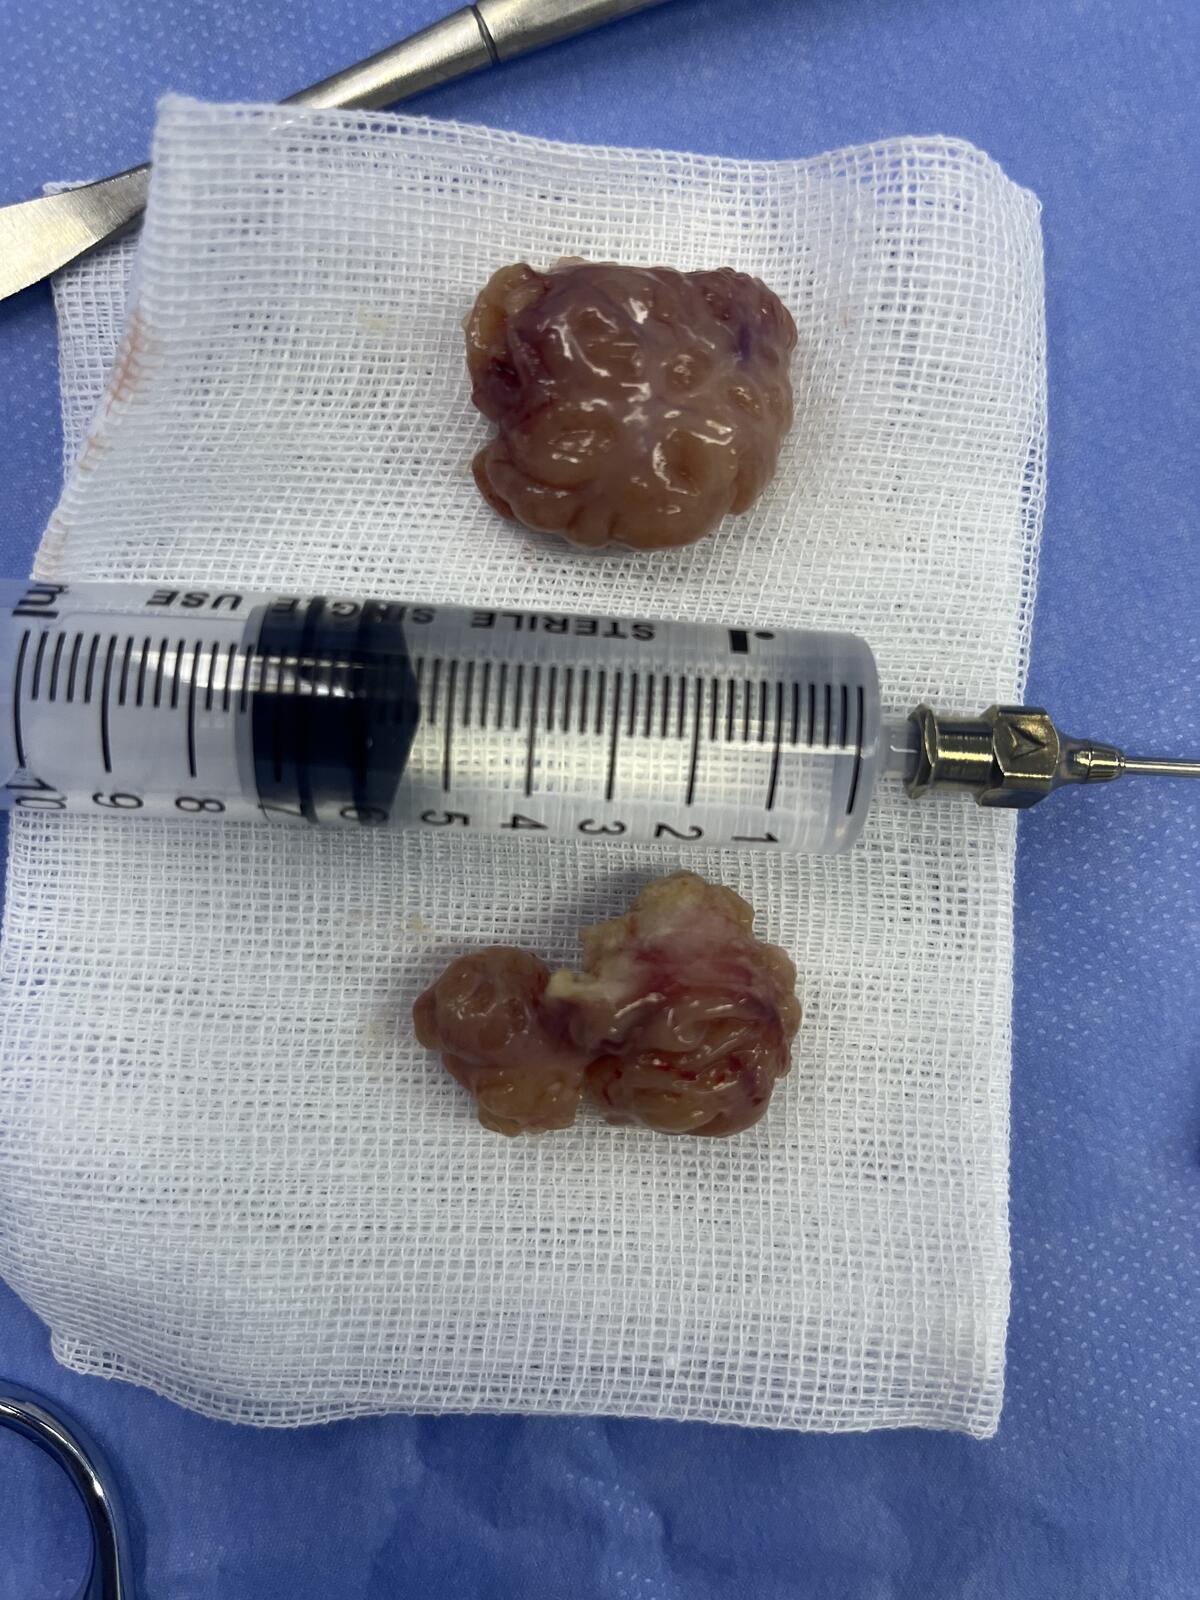

肥大扁桃体

切除肥大扁桃体